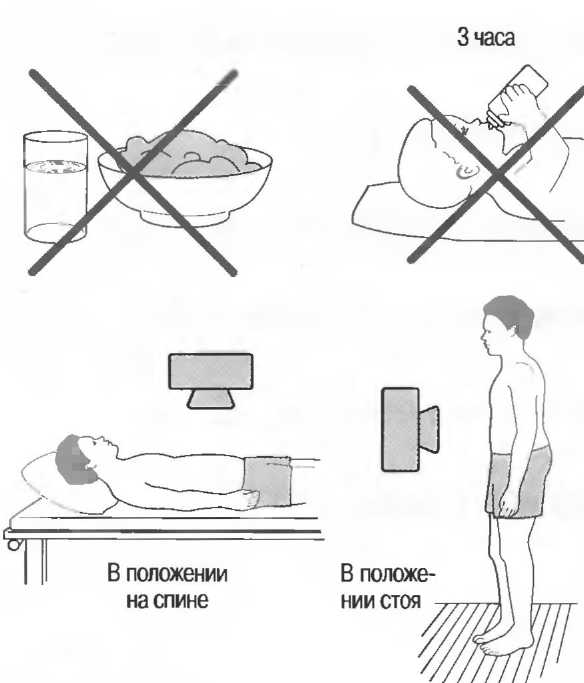

1. Подготовка

Пациент не должен пить и есть в течение 8 ч перед исследованием. Если жидкость необходима для предотвращения дегидратации, можно давать пациенту только воду. При острой симптоматике исследование можно проводить без подготовки. Детям, если позволяют клинические условия, пища и вода не даются в течение 3 ч до исследования.

При более углубленном исследовании, если нет клинических противопоказаний, может быть полезным дополнительный прием воды, особенно при исследовании поджелудочной железы, нижних отделов живота и таза.

2. Положение пациента. Пациент может лежать в удобной позе на спине. Под голову можно положить маленькую подушку, в случае выраженного напряжения передней брюшной стенки подушечку можно поместить также под колени пациента.

Намажьте живот гелем.

Пациенту разрешается дышать спокойно, однако при исследовании отдельных органов требуется задержка дыхания на вдохе.

3. Выбор датчика. Используйте датчик 3,5 МГц для взрослых и датчик 5 МГц для детей и худых взрослых. Предпочтительны конвексные или секторные датчики.

4. Установите правильный уровень общей чувствительности. Начинайте исследования, поместив датчик центрально в верхней части живота под мечевидным отростком и попросите пациента глубоко вдохнуть и задержать дыхание на вдохе.

Поверните датчик направо до того, как начнет визуализироваться печень. Отрегулируйте чувствительность, чтобы изображение имело нормальную однородную зхоструктуру. Должна быть хорошо различима высокоэхогенная линия диафрагмы сразу за задними отделами печени (рис. 27а).

Воротная и печеночные вены должны визуализироваться как трубчатые структуры с анзхогенным просветом. Стенки воротной вены высокозхогенны, но стенки печеночных вен практически не видны (рис. 276).

Рис.27а. Продольный срез. Неизмененная печень и диафрагма.

Рис.27б. Продольный срез: печеночные и воротная вены.

Рис.27в. Поперечный срез через неизмененную печень.

Техника сканирования

После того как вы отрегулировали чувствительность прибора, медленно передвигайте датчик от средней линии вправо, через каждый сантиметр останавливаясь и проверяя изображение. Проверяйте на различных уровнях. После того как вы исследовали правую сторону, таким же образом исследуйте и левую сторону. При этом датчик нужно направлять в различных направлениях, для того чтобы лучше локализовать объект и получить больше информации. Очень важно исследовать всю брюшную полость: если после изменения угла наклона датчика верхняя часть печени или селезенки не визуализируются, необходимо проводить сканирование через межреберные промежутки.

После этих поперечных сканов разверните датчик на 90° и снова начните сканировать от мечевидного отростка. Снова локализуйте печень и при необходимости попросите пациента задержать дыхание на глубоком вдохе, чтобы визуализировать ее лучше. Убедитесь, что уровень чувствительности установлен правильно. При необходимости наклоняйте датчик по направлению к голове пациента. Проводите исследование по межреберным промежуткам.

Ниже ребер держите датчик в вертикальном положении и передвигайте его по направлению к ногам (каудально). Повторите в различных вертикальных плоскостях по всему животу.

Если какая-нибудь часть живота визуализируется плохо, можно проводить исследование в положении больного сидя или стоя. При необходимости проводится исследование в положении пациента на боку с приподнятой головой; чаще зто используется при исследовании почек и селезенки. Не стесняйтесь поворачивать пациента. Если вы заподозрили патологию, используйте технические приемы, описанные в соответствующих разделах.

Важно визуализировать:

|

1. |